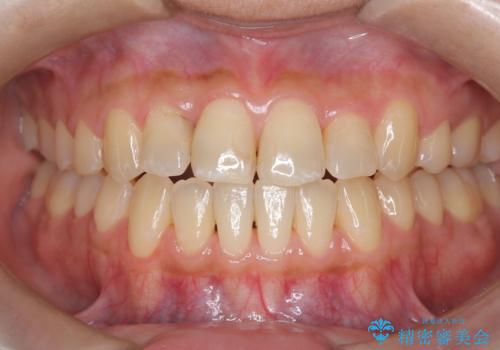

[マウスピース矯正] 海外留学中でも可能な矯正治療

担当医 大元洋佑